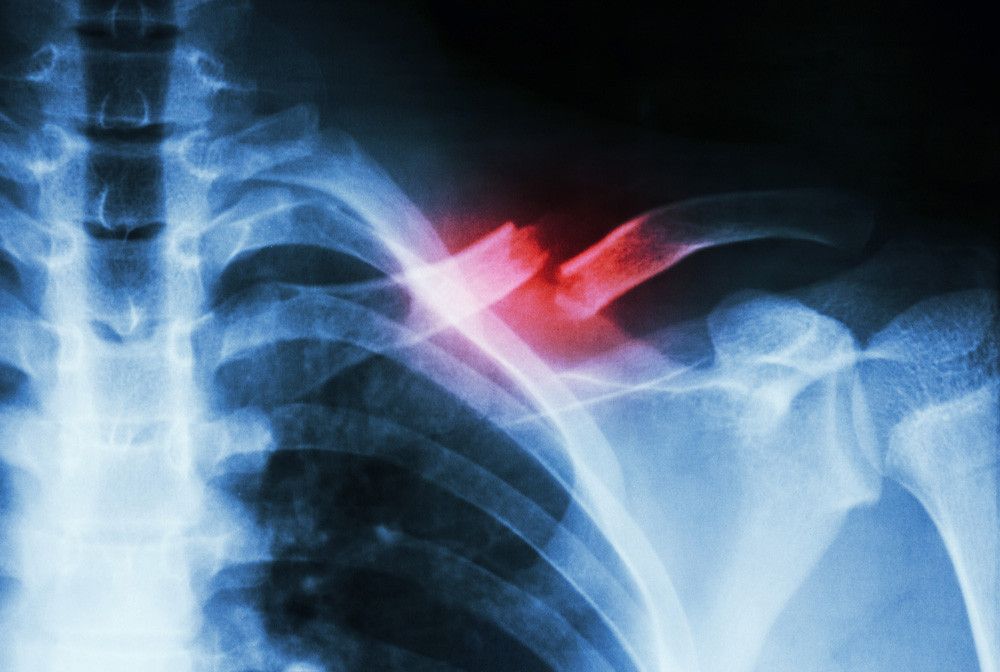

:format(webp)/article/AJA9cCuhunCznnKgom8Fi/original/081757200_1531379499-Patah-Tulang-Selangka-By-Puwadol-Jaturawutthichai-shutterstock.jpg?w=256&q=100)

Apabila Anda curiga korban kecelakaan mengalami patah tulang, berikut ini adalah tahapan pertolongan pertama yang bisa Anda berikan.